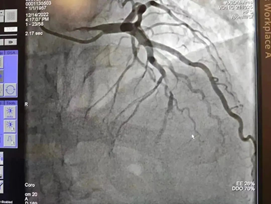

心血管造影

术前